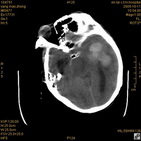

病人杨XX,男,青云街道办事处路踏泉村,住院号51666,CT号:104770。病人因“高血压脑出血”在新泰市人民医院住院治疗5天,治疗效果不佳转入我院,复查CT示左基底节血肿,病人昏迷状态,给予血肿清除术,术后2天复查CT,血肿完全清除,病人恢复好,治疗效果满意。附病人术前术后CT片资料如下。

术前CT

术前CT1 术前CT2 术前CT3 术前CT4

术前CT5 术前CT6 术前CT7 术前CT8

术前CT9 术前CT10

术后46小时复查CT

术后46小时复查1 术后46小时复查2 术后46小时复查3 术后46小时复查4

术后46小时复查5 术后46小时复查6 术后46小时复查7 术后46小时复查8

术后46小时复查9